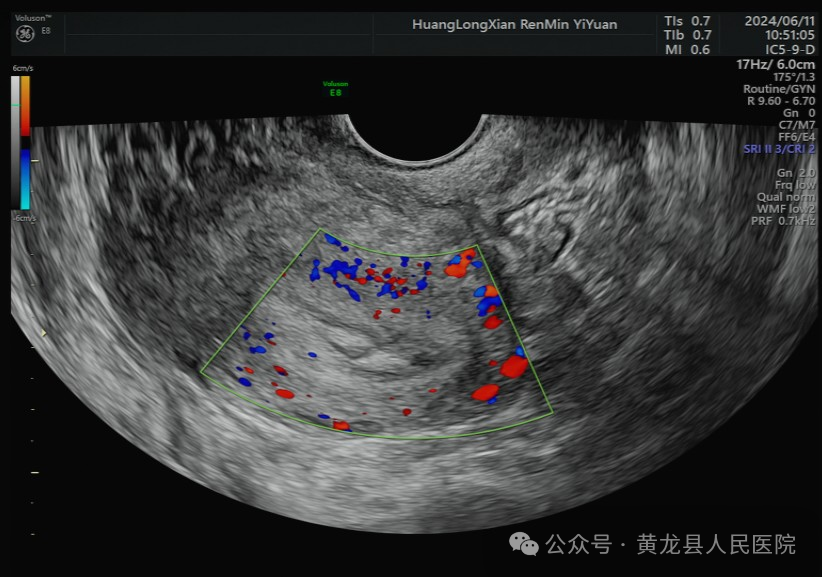

据统计,子宫内膜息肉在妇女子宫异常出血情况的诊断中占比:绝经前10-40%,绝经后10.1-38%,这些数据显示,子宫内膜息肉是女性子宫异常出血中的一个重要因素,尤其在绝经前后的女性中最为常见。随着医疗技术的不断提高和超声医疗设备的更新,图像清晰度不断提升,使超声在各个器官的诊断有了突飞的进步,特别是阴道超声的应用,对子宫内膜息肉的诊断也变得更加准确。

我院超声科于2019年引进美国GE Voluson E8四维彩超诊断仪,该设备是国内外彩超领域的佼佼者,是兼具优异图像和快捷工作效率的超声系统,为获取优异图像提供了技术保证,设备在产前筛查、胎儿心脏、生殖、妇科盆底超声、围产超声等领域均处于世界先进水平,可进行各类妇产科疾病成像,为女性健康保驾护航。其腔内探头是子宫内膜息肉检出率的主要功臣。